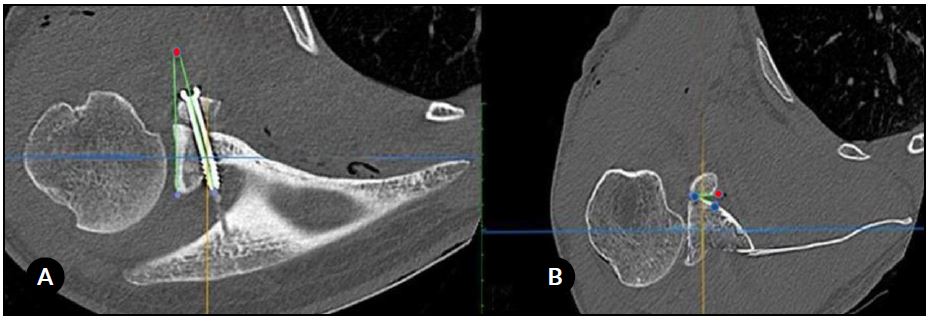

Se mostraron simultáneamente en la misma pantalla las imágenes en 2 planos (sagital y axial). Luego se realizaron las siguientes 4 medidas para cada paciente: (A) la posición del injerto coracoideo en el plano sagital, (B) la posición del injerto en el plano axial, (C) la dirección de los tornillos (ángulo), y (D) el ángulo de contacto (Figs. 1 y 2).

La posición del injerto coracoideo en el plano sagital se definió como el porcentaje del injerto ubicado debajo del ecuador de la cavidad glenoidea. Dividimos los resultados en 4 grupos: A (80-100 % por debajo del ecuador), B (60-79 %), C (40-59 %) y D (<40 %).

En el plano axial, el injerto coracoideo se consideró “al ras” cuando el borde lateral del injerto estaba entre 1 mm lateral y 4 mm medial a la línea articular; “medial” cuando estaba >4 mm medial a la línea articular; y “prominente” cuando era >1 mm lateral a la línea articular. El ángulo α se definió como el ángulo entre el eje del tornillo y el hueso subcondral glenoideo. Finalmente, el ángulo de contacto fue el ángulo formado entre la superficie posterior del injerto coracoideo (medido entre los 2 tornillos) y el cuello anterior de la glena. Se consideró contacto completo si el ángulo era ≤4 e incompleto cuando era >4. Si el espacio entre el injerto y la glenoides era >1 mm, asumimos que no existía contacto.16

Figura 1. Evaluación del injerto coracoideo. A) Plano sagital en relación con el ecuador de la glena. La flecha negra indica la longitud total del injerto coracoideo, mientras que la flecha roja muestra la parte del injerto que se encuentra debajo del ecuador glenoideo. B) Plano axial (posición mediolateral). La línea negra es tangente al hueso subcondral de la glenoides mientras que la línea roja indica la distancia entre la línea negra y la cara más lateral del injerto coracoideo.